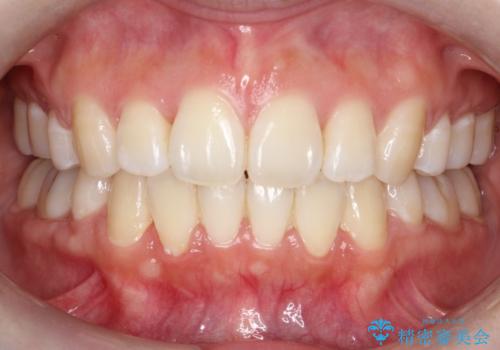

【ハーフリンガル】口元を下げたい!

- 口元が出ていることを主訴に来院されました。

歯を抜いてスペースを作ることで、前歯を下げることができました。

ハーフリンガルということで治療期間が3年近くかかりましたが、口元もしっかり下がり満足していただきました。